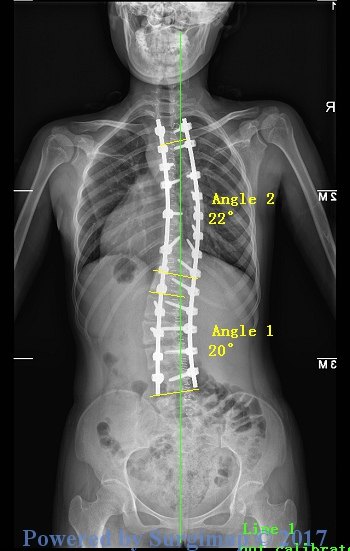

手术的效果是显而易见的,胸弯腰弯的角度从100°和70°分别矫正到22°和20°!

外形的矫正也是明显的,S形的背部消失,躯干不再偏移,双肩平衡,而且术后小虹的身高也增加了3cm!